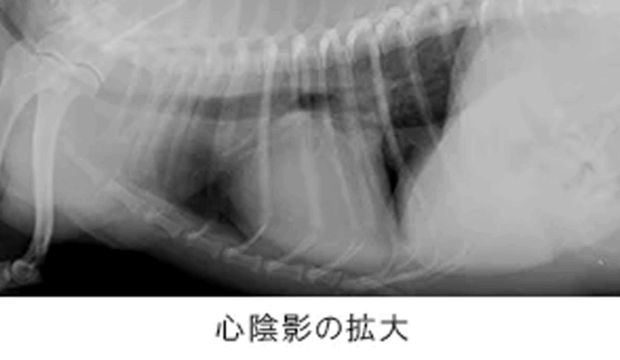

猫 MIX 18歳

呼吸が速い

呼吸促迫、食欲低下

胸部レントゲンにより、肺野のびまん性不透過性亢進像・左側前葉部の無気肺が確認され、当初肺炎が疑われていましたが心臓超音波検査により拘束型心筋症と診断。

| 猫で2番目に多い心筋症の一つです。強心剤の内服・利尿剤に良好に反応し呼吸状態は改善、元気・食欲ともに回復し良好な一般状態を維持しています。 拘束型心筋症は大動脈血栓塞栓症を併発することがあるため、抗血栓薬を用い血栓の予防を合わせて実施することが大切です。 |